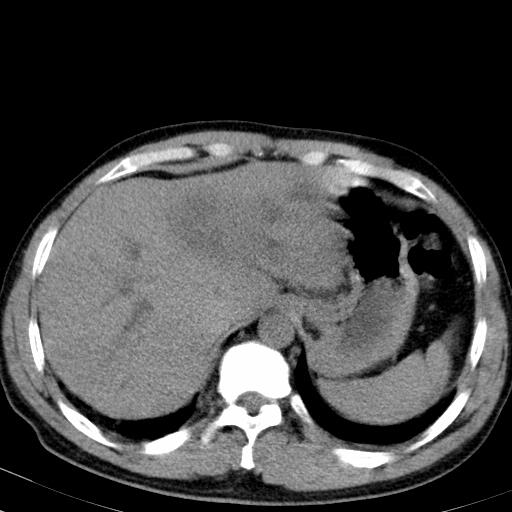

患者上腹部疼痛一月余,伴巩膜黄染;

实事求是的说,强化效果很一般,重点部位应重点观察,但有一点可以明确:肝门部胆管细胞癌。

考虑肝左叶胆管细胞癌侵犯肝门区并肝内胆管及肝总管扩张。

肝左叶肿块清度增强,所在的叶胆管扩张。考虑胆管细胞癌。